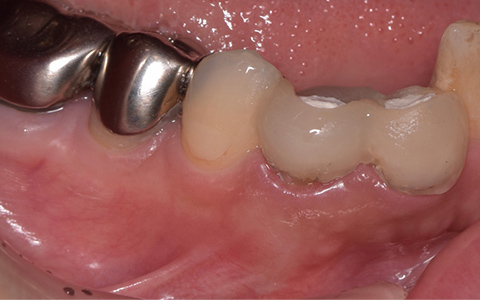

治療前

治療後

黄色い矢印の歯が治療前の対象歯です。レントゲンで観察すると、歯の根のお薬が充分には入っていないようです。

麻酔をして歯の中をマイクロスコープで観察すると、元々あった3つの根だけでなく「もう一つの4番目の根」があったのです。根管治療自体は容易に行えましたが、歯の中を明るく拡大できるマイクロスコープを持っていない歯医者さんでは見つけるのが困難だと思われます。この4つ目の歯の根を治療することにより痛みは消失し「抜歯してインプラント」になるという悪循環に陥らず済みました。根管治療はマイクロスコープを使って精密に、また丁寧に行えば歯を長く保たせることができる治療です。やはり神経自体を残すという選択が、歯の保存にとって一番良いということは間違いありません。

| 費用 | デンタルドック:55,000円 根管治療(奥歯):176,000円 MTAセメント:33,000円 歯の土台:33,000円 合計:297,000円 |

|---|---|

| リスク・副作用 | 治療中に一時的な咬合痛や冷温水痛、若干の歯肉の腫れ、発赤などを生じることがあります。また仮歯の時期には仮歯の脱離や破損の可能性、舌感などに違和感を覚えることがありますが、本歯に移行するまでに通常消失します。 ※すべて症例による違いや個人差があります。 |

※表示金額は全て税込みです。